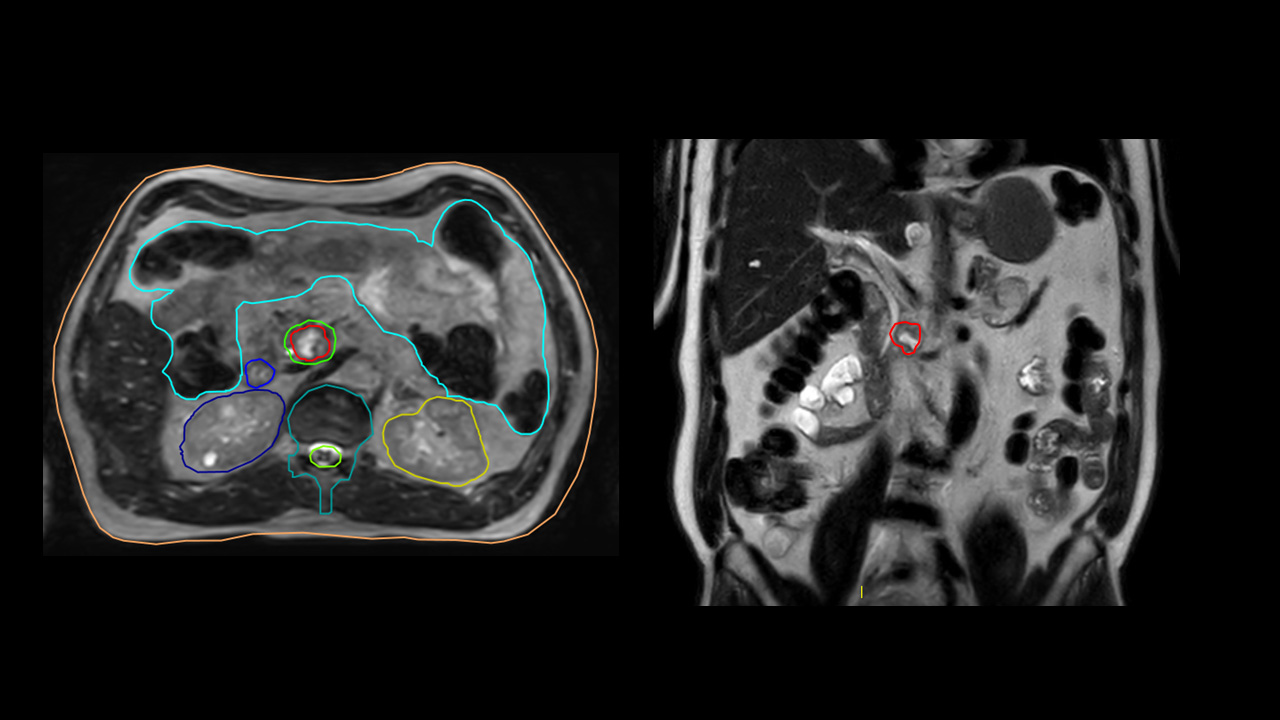

Image-Guided Radiation Therapy. IGRT involves repeating imaging procedures to confirm the patient's position and reduce the risk of missing the target. This is particularly important in the treatment of pancreatic cancer, where internal organs can shift both during the setup phase and throughout the treatment itself. A German study on adaptive MR-guided radiotherapy for abdominal lesions found that the violation of dose constraints increased significantly, from 6.9% with the adapted plan to 30.2% with the pre-irradiation distribution.[33] This dramatic rise was attributed to intrafraction movement.

Targeted Therapy